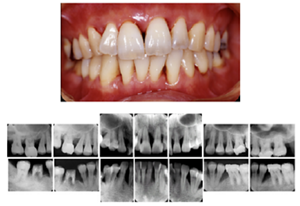

図8 長期メインテナンスの実際

1999年初診。年齢32歳 女性、“はぐきが腫れる”という主訴で来院されました。若い年齢にもかかわらず重度歯周炎にすでに罹患をしていました。

治療後21年。右上第1大臼歯は治療時に抜歯となってしまいましたが、治療完了後は定期メインテナンスを継続し、歯周組織は安定、一本の歯も失わずに現在まで経過しています。